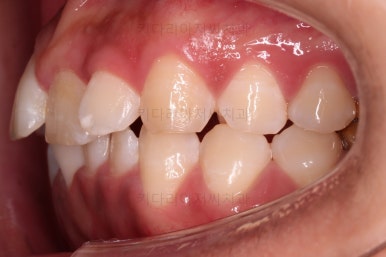

악궁확장 이후에 교정장치를 부착하고 치열을 가지런하게 해줘요.

이번에 사용한 장치는 엠파워 메탈이라고 하는 자가결찰 메탈 장치입니다.

거듭 말씀드렸지만 메탈이라고 다 옛날의 구식 장치가 아니에요.

"자가결찰" 인지 아닌지 여분가 훨씬 중요한데요.

"자가결찰" 메탈장치라면 치료효과가 좋은 "자가결찰"장치의 한 종류이므로 기능이 매우 좋은 장치랍니다.

장치 부착 이후의 느낌도 봐주시고요.

치열이 점점 가지런해지죠?